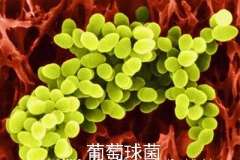

葡萄球菌导致的盆腔炎如何用药

大肠杆菌导致的盆腔炎怎么治疗

大肠杆菌是人和动物肠道中的一种细菌,为正常的菌群,但有些大肠杆菌具有毒性,会引起各种疾病的发生,比方说女性的盆腔炎。导致盆腔炎的主要病原体除了大肠杆菌外,还有葡...